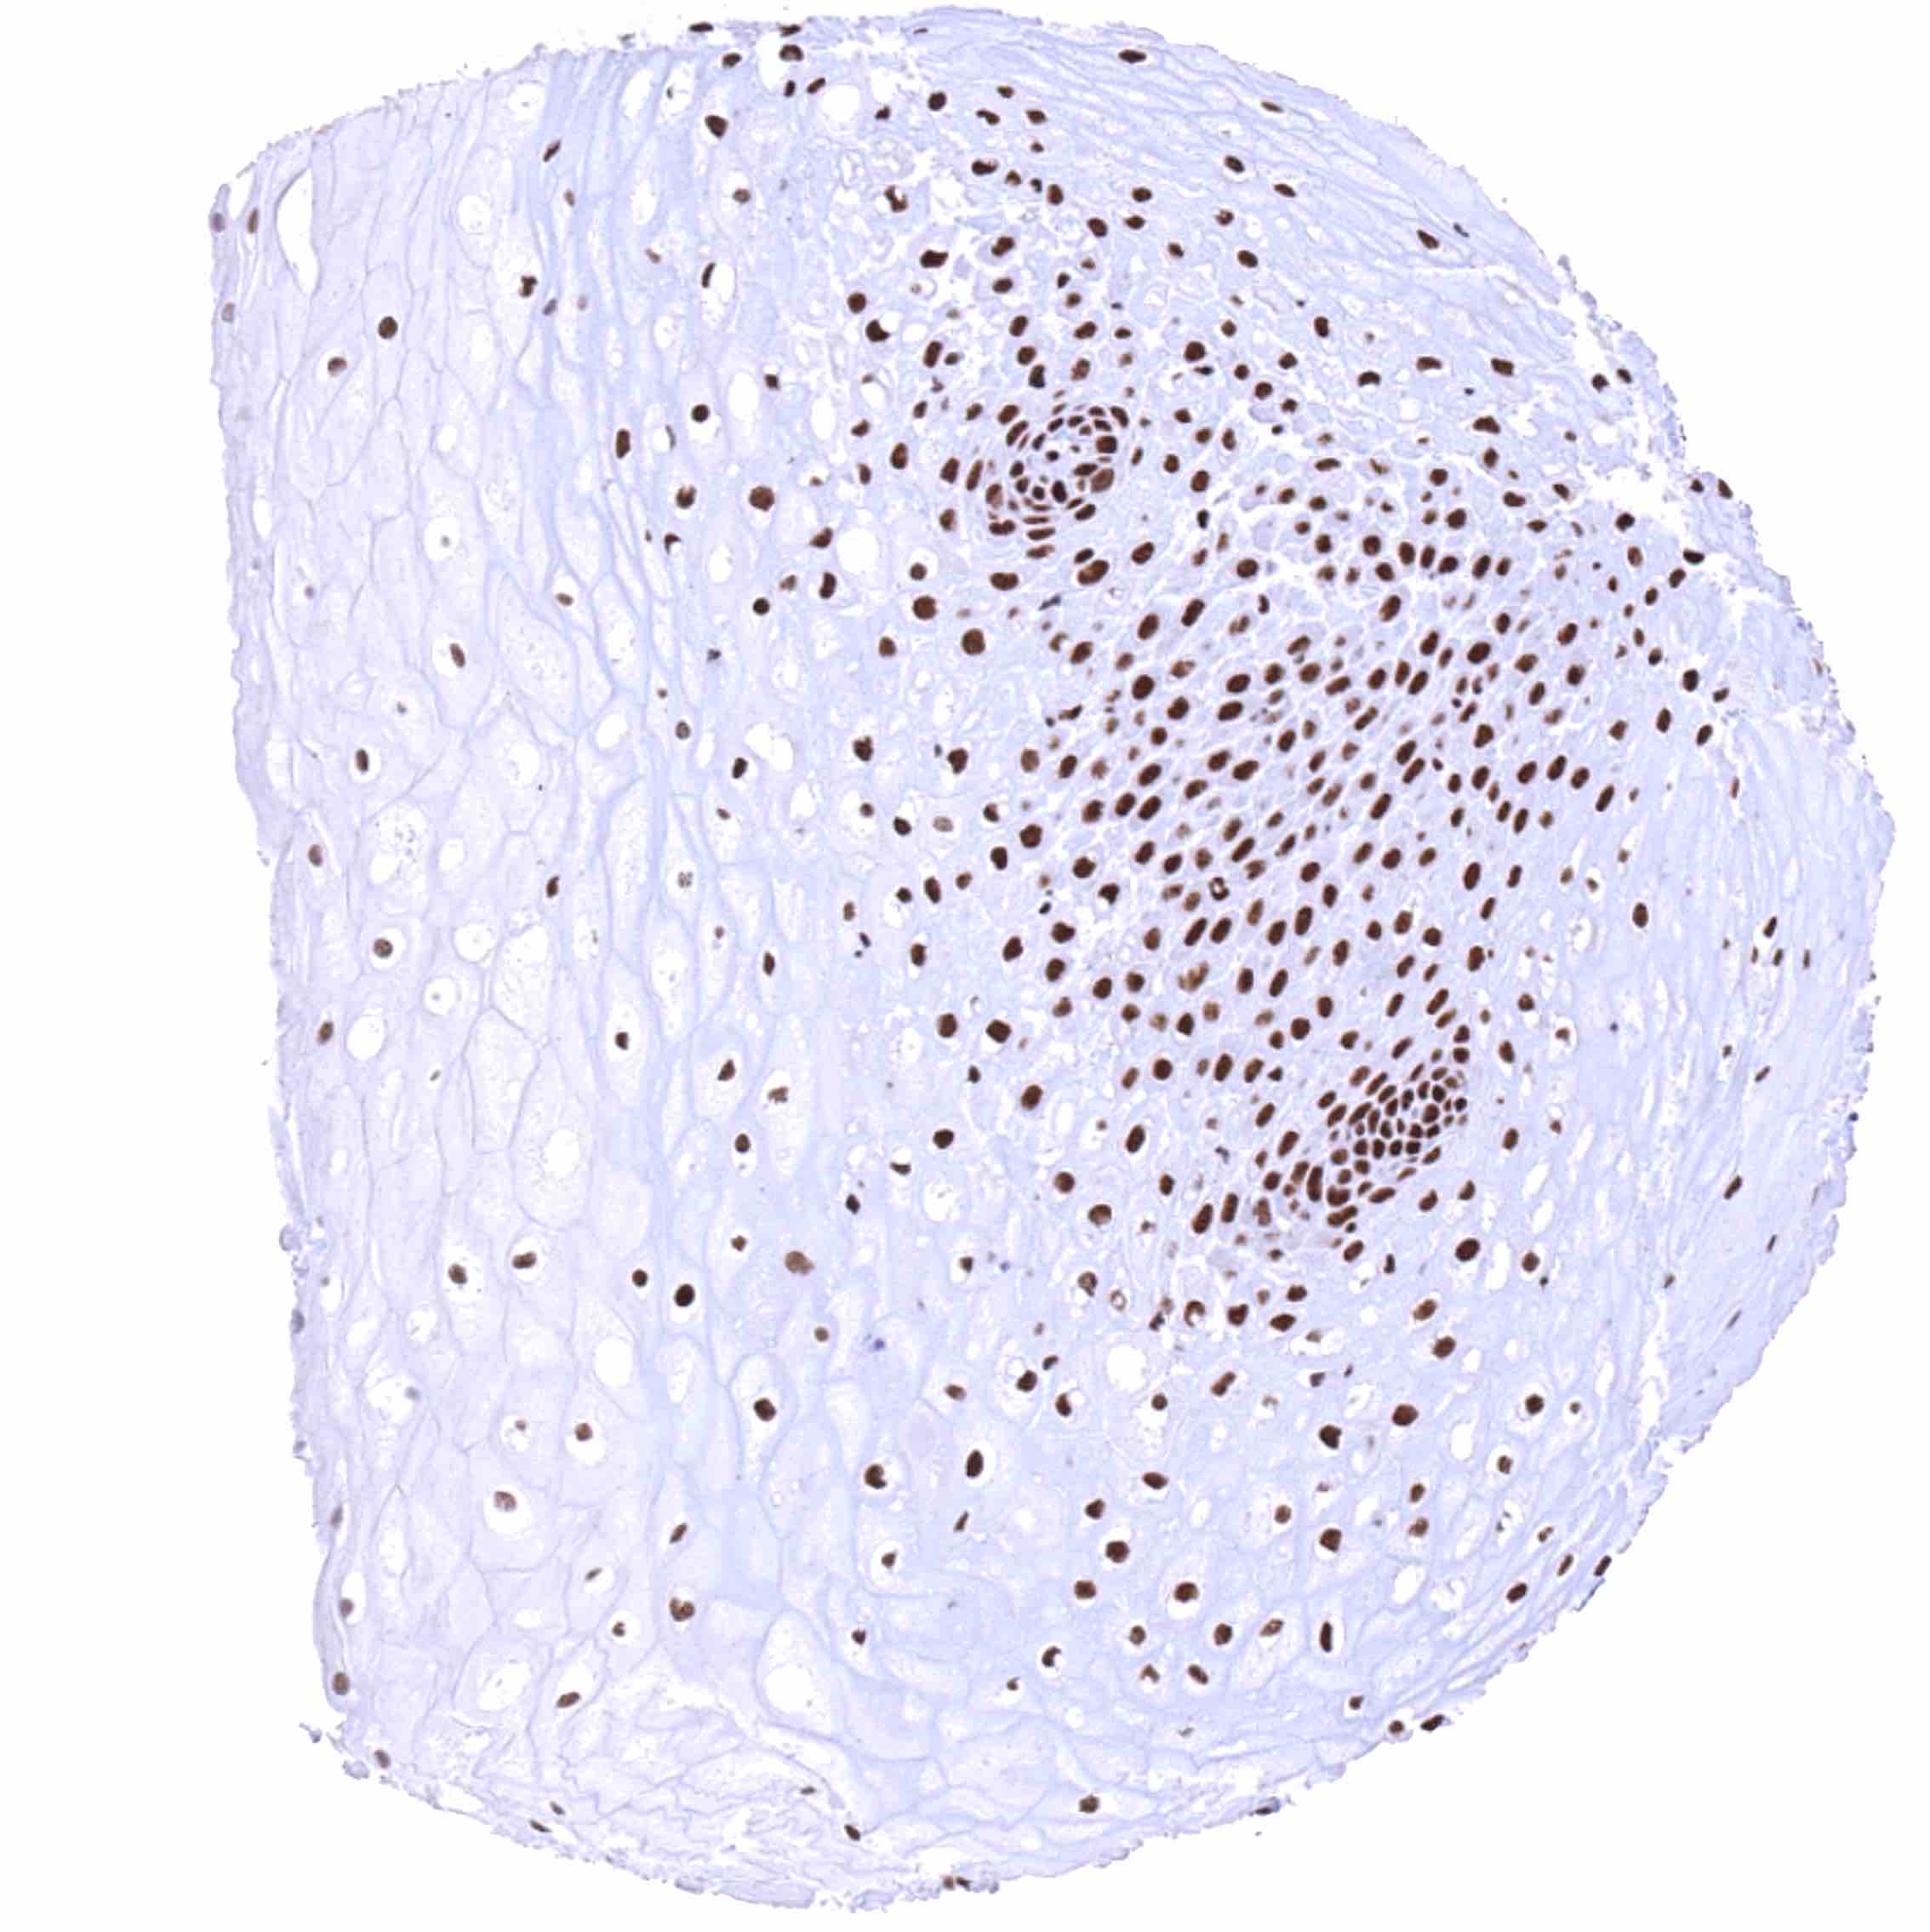

Testis – The level of nuclear BRD4 staining decreases with maturation of germ cells.